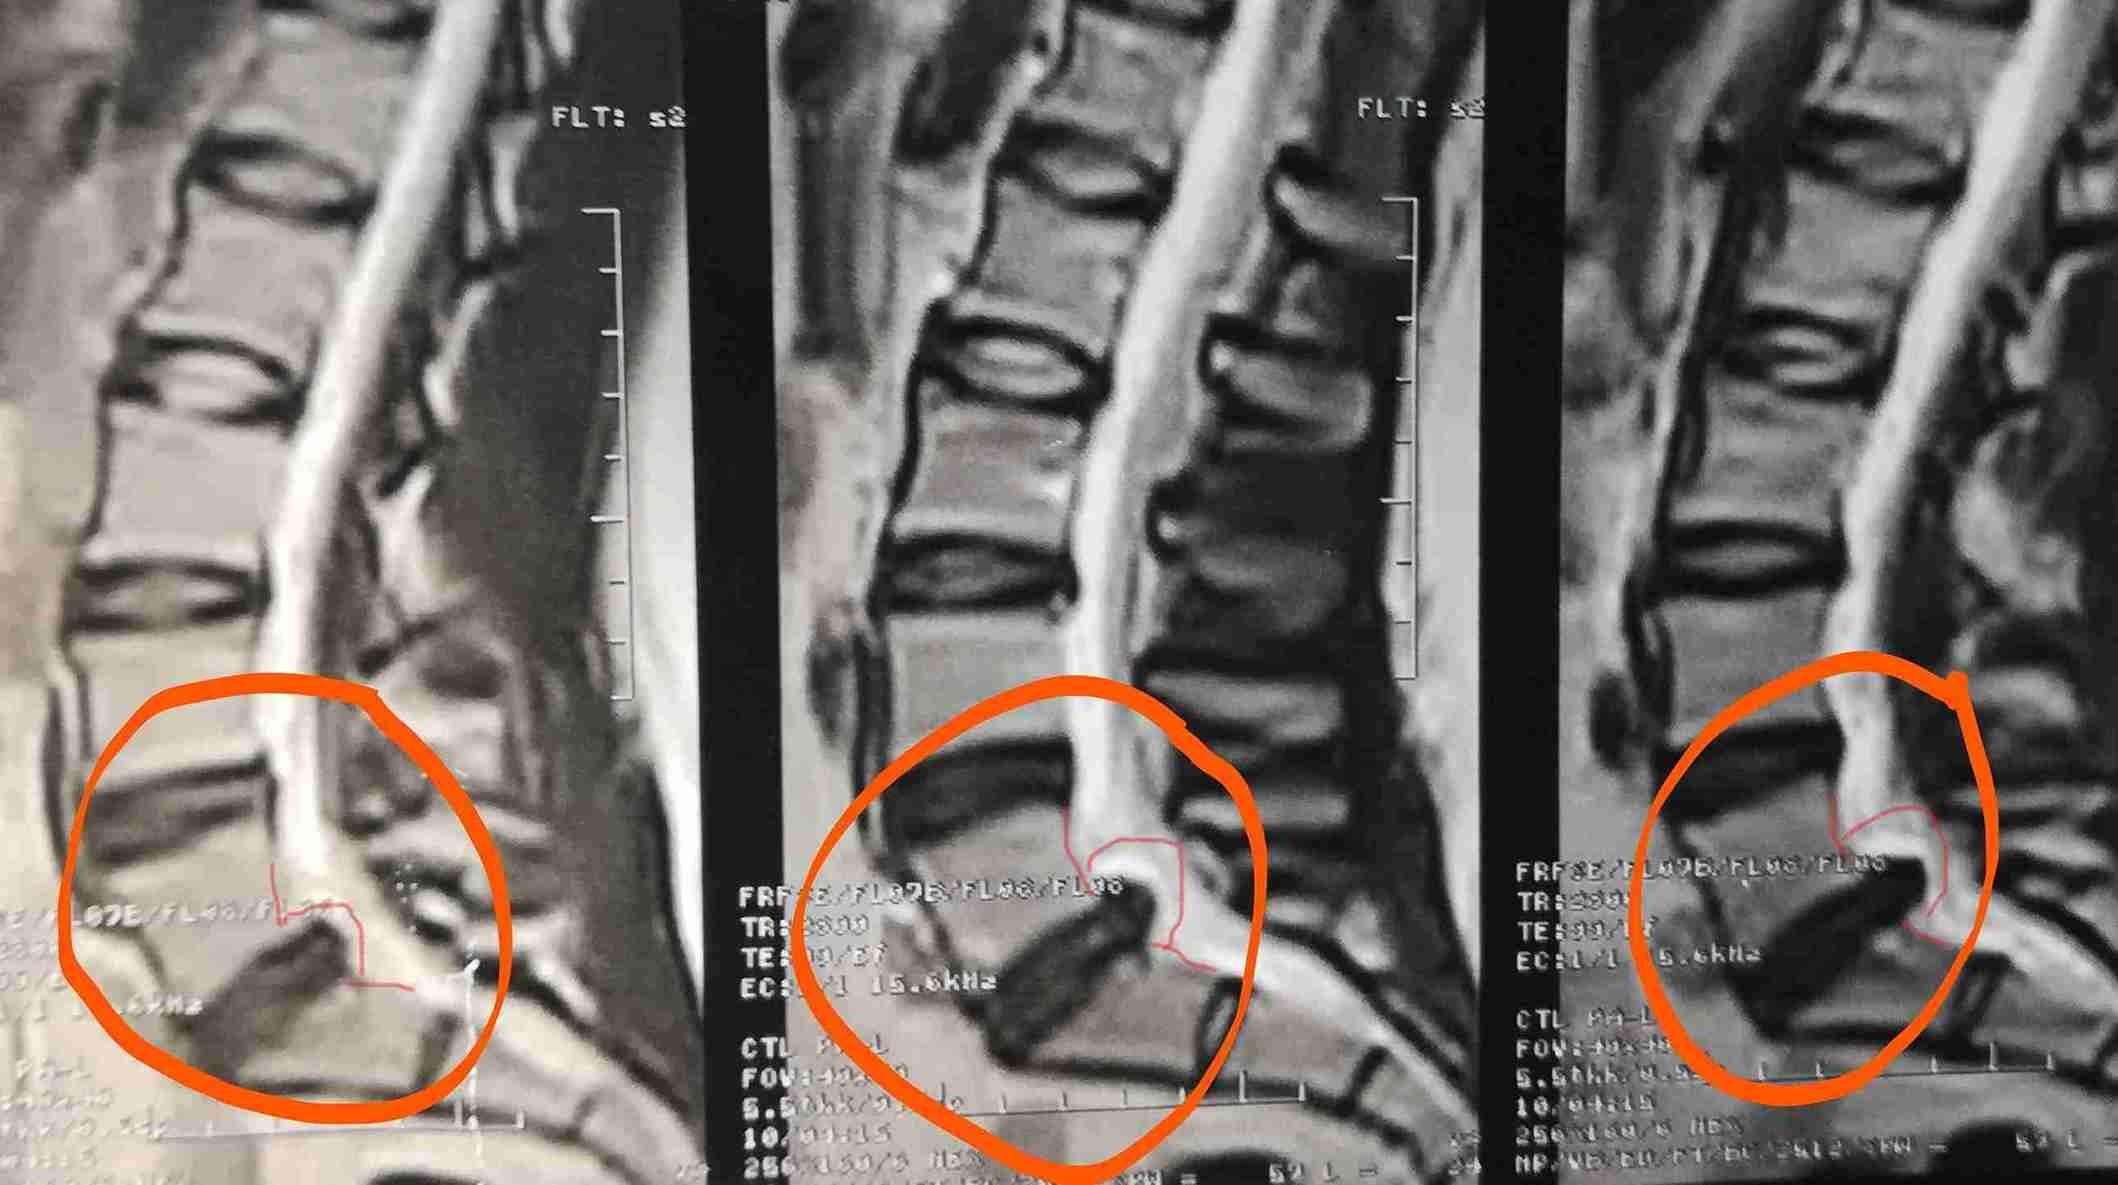

A successful surgery was performed to treat a herniated disc accompanied by spondylolisthesis. This condition causes severe back and leg pain due to pressure on spinal nerves, significantly affecting the patient's mobility and walking ability.

• Removing herniated disc causing nerve compression

• Relieving pressure on nerve roots